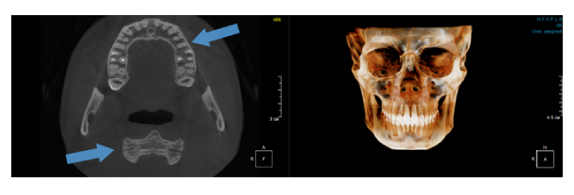

Когда мы отправляем пациента на проведение рентгенологического исследования, то подвергаем его определенному риску. Именно это нужно осознавать, так как в радиологии нет минимально безопасной дозы, поэтому любое назначение должно быть обоснованным. В связи с этим поле обзора является достаточно принципиальным параметром. Если вы врач-терапевт, занимающийся эндодонтией или ортопед, который решил оценить состояние зубов перед протезированием, то вы должны понимать, что проведение исследования с полем обзора 10x10 см будет гораздо информативнее нежели большие снимки (18x16 см и выше). В первую очередь это связано с размером вокселя, о нём я напишу чуть ниже, а второе это то, что вам придется увеличивать изображение по каждому корневому каналу, и от этого вы будете терять в качестве снимка (рис. 1). И ситуация наоборот, если вы ортодонт, то чтобы использовать весь диагностический потенциал, а также возможность загрузить данные для расчёта 3D цефалометрии, то вам нужны снимки, захватывающие весь лицевой отдел черепа. Таким образом, дентальный томограф должен обладать возможностью проведения исследований с разным FOV, обеспечивая нужды всех специалистов. Если ваша клиника базируется на терапевтическом, хирургическом и ортопедическом приёме, то на мой взгляд, можно рассмотреть дентальные томографы с полем обзора 10x10 см или 16x10 см. Последний больше актуален для тех, кто работает с ВНЧС, так как антропометрически в 16 см даже у брахицефалов сустав должен попадать. Если в клинике есть ортодонтическое направление, функциональная стоматология, ЛОР-практика или ЧЛХ, то, безусловно, вышепредставленные снимки не будут отражать всех данных, которые необходимы для диагностики и планирования лечения. Здесь лучше рассмотреть конусно-лучевые компьютерные томографы с зоной сканирования 18x16 или 20x20 см. Особо стоит отметить понятие «сшивки». Есть дентальные томографы, которые делают один цельный снимок размерами, которые описаны выше, а есть аппараты, которым нужно провести две экспозиции и сшить изображения вместе, чтобы получился необходимый объём исследования. Как правило, вторые томографы чуть дешевле, но всё зависит от того, насколько вам нужна максимальная точность исследования. Если при сшивке челюсти и зубы, как правило, совмещаются практически идеально, то на уровне позвоночного столба происходит наслоение тканей и от него уже не избавиться (рис. 2). Второй отрицательный момент – это износ оборудования, логично, что он будет быстрее, так что экономия средств — это ещё спорный вопрос.

Рис. 1. Представлены два исследования (10x10 см и 20x20 см). На обоих изображениях хорошо видна канально-корневая система зубов, но, если масштабировать второе исследование, то качество неминуемо снизится, как и диагностическая эндодонтическая эффективность.